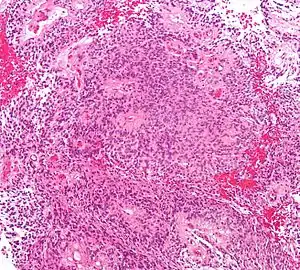

Micrograph of an ependymoma. H&E stain.

Ependymomas are composed of cells with regular, round to oval nuclei. There is a variably dense fibrillary background. Tumor cells may form gland-like round or elongated structures that resemble the embryologic ependymal canal, with long, delicate processes extending into the lumen; more frequently present are perivascular pseudorosettes in which tumor cells are arranged around vessels with an intervening zone consisting of thin ependymal processes directed toward the wall of the vessel.[2]